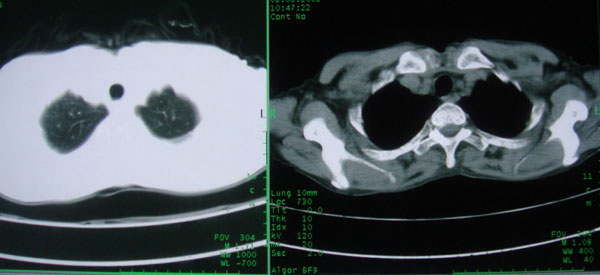

标题: CT15046:F59Y,咳嗽间断咳血丝痰就诊. [打印本页]

标题: CT15046:F59Y,咳嗽间断咳血丝痰就诊.

咳嗽\间断咳血丝痰就诊.